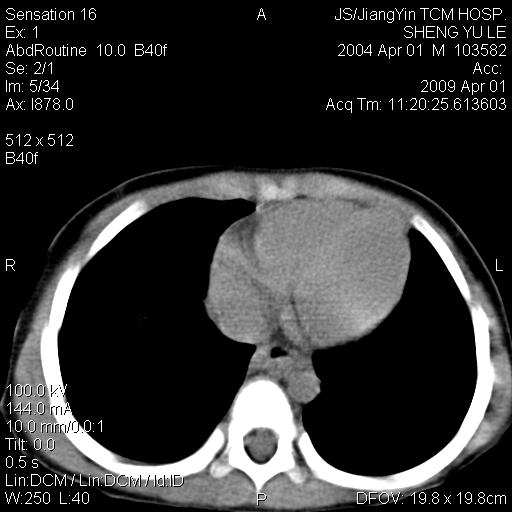

m,5岁。尿痛尿频数天。既往无病史。ct平扫腹盆腔积液。膀胱壁明显增厚。另可见心包增厚。wbc5万,骨髓穿等结果。请指教。

膀胱影像表现结合临床应该是急性膀胱炎症,但为什么有腹水呢?双肾输尿管无扩张,泌尿系压力应该不大不至于引起尿外渗,应该是腹膜感染引起的,但楼主没有提及相关症状,腹膜及膀胱结核?患者白细胞5万(结核不至于这么高啊),脾脏增大,是不是有白血病?进一步检查。。

腹水,膀胱壁增厚,wbc5万,结合临床,支持感染性疾病---感染性腹膜炎、腹水,急性膀胱炎,败血症。期待结果。